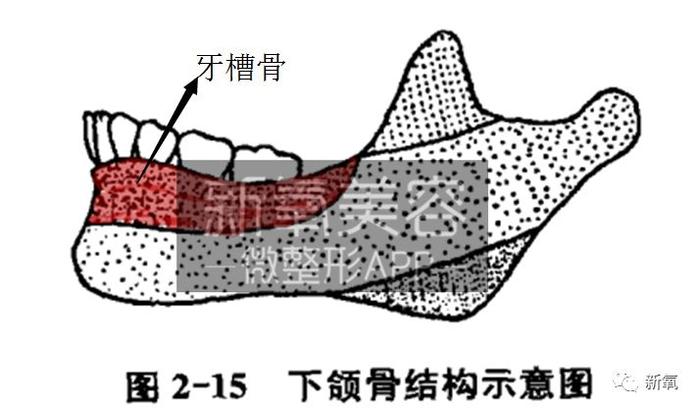

看下图,大家可以简单的理解为,下颌骨原本仅有下图中标黄的管状基础骨体部分。它的生长和一般长骨的生长类似,在发育期两端前后延长。

可是,由于咬肌、翼内肌、以及颞肌等的运动结果,形成了下颌角和冠状突(下图绿色部位)。

觉得好像有点懵的话看这个图。伴随着这个肌肉运动,使得下颌角和冠状突变得明显。

最后叻,就是这个涂红的位置,因为后来牙齿的萌出形成了这个区域的牙槽突。也就是和今天文章那么多牙齿内容都相关的一个骨体位置啦。

(下颌骨部分的理论依据和骨骼原图来源:《现代口腔正畸学》第四版)